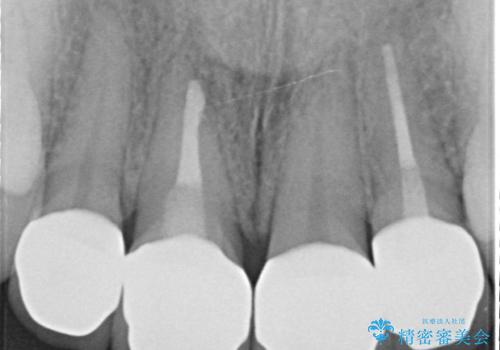

- 前歯の色や長さ、歯茎との隙間の金属が気になるのでセラミックで治療したいといらっしゃった方の症例です。

見た目改善のため、前歯4本をオールセラミッククラウン(スペシャル)で補綴しました。

右上1と左上2は再根管治療を行っております。